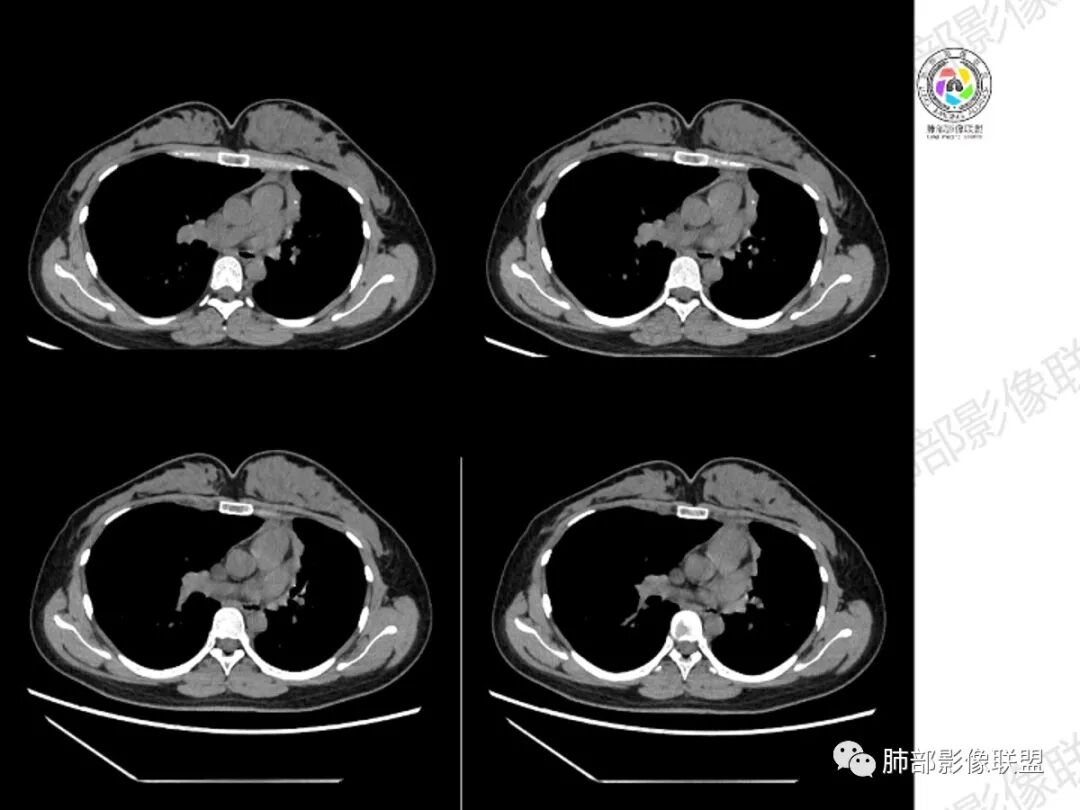

年轻女性,慢性病程,左上叶纵隔旁大片实变,心脏纵隔左移,左主及左上叶支气管变窄呈针孔样,实变内可见斑点状钙化,显著不均匀强化,内可见低密度粘液拴,显著强化不支持TB,左上叶不张在腺癌少见,综合病变部位及强化表现考虑粘液表皮样癌,其次考虑类癌

女性,29岁,咳嗽咳痰,痰中带血1月余,CT示左肺尖胸膜下纵隔旁不规则实变影,内部可见小点状钙化灶,支气管略狭窄,增强可见低密度不强化区,粘液栓?实性成分明显不均匀强化,局部与左肺动脉分界不清,另左肺可见多发小结节,考虑为恶性,黏表可能,鉴别结核

年轻女性,咳嗦咳痰伴咳血1月多,ct可见纵隔左移,左肺容积减小,左肺上叶可见一不规则实变影,朝肺内侧边界清楚,部分边缘与纵隔界限模糊,临近支气管堵塞,内见点状钙化,增强不均匀强化,内可见多个低密度区,粘液?并与左肺动脉界限模糊,似受侵,考虑恶性,黏表?但病灶远端有多发小结节,卫星灶?结核待排

胸部CT:左肺体积缩小,左肺上叶前段纵隔旁胸膜下大片实变影,边缘清楚、匀齐、平直收缩,部分略膨隆,周围多发结节、树芽卫星灶,纵隔窗病灶与纵隔胸膜黏连,实变内多发点状钙化。平扫密度尚均匀,增强扫描不均匀明显强化,多个低密度区,呈仙人掌样,伴有条状血管影,考虑慢性炎症伴左上叶前段支气管闭塞,TB?鉴别黏表、腺癌等。